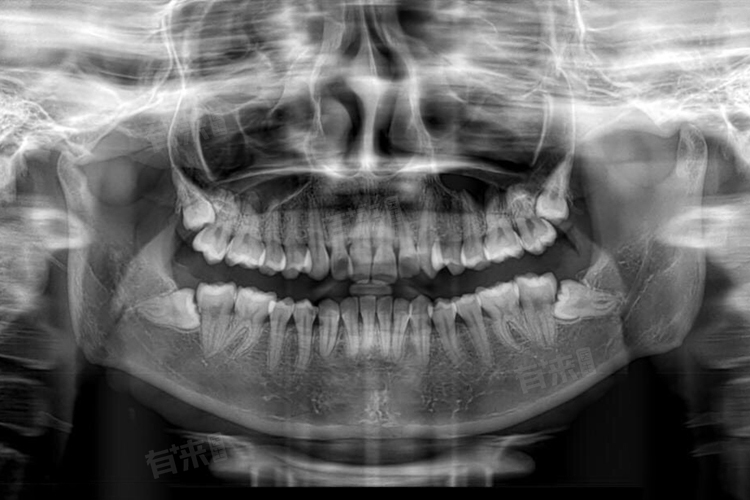

拔后槽牙的价格通常在200元到2000元不等,主要取决于牙齿的生长情况、拔牙的难度以及所使用的器械和材料等因素。如果后槽牙是正常萌出,位置比较正,与周围组织没有粘连,拔牙过程相对简单,拔牙时间较短,对医生的技术要求也相对较低,费用通常在200-500元。

- 当后槽牙倾斜生长,部分被牙龈或牙槽骨覆盖时,拔牙难度会有所增加。医生可能需要先切开牙龈,去除部分牙槽骨,才能将牙齿拔除。这个过程需要使用到手术刀、骨凿等器械,并且对医生的技术要求较高,手术时间也会相对较长,所以费用一般在500-1000元。

- 埋伏阻生的后槽牙完全埋在牙槽骨内,需要通过手术切开牙龈、翻瓣、去骨等一系列操作才能暴露牙齿并将其拔除。这种情况下,手术创伤较大,术后恢复时间较长,还可能需要使用抗生素、止痛药等辅助治疗,因此费用较高,通常在1000-2000元。

- 后槽牙的牙根形态复杂多样,有的牙根较短且直,有的牙根则较长、弯曲或分叉较多。牙根较短直的牙齿相对容易拔除,而牙根复杂的牙齿在拔除时需要更精细的操作,以避免牙根折断或损伤周围组织,所以费用会因牙根形态的不同而有所差异。一般来说,牙根复杂的后槽牙拔牙费用会比牙根简单的高出200-500元。

- 使用常规的拔牙器械,如牙钳、牙挺等进行拔牙,费用相对较低。这些器械成本较低,且操作相对简单,适用于拔牙难度较小的情况。对于复杂的拔牙病例,可能需要使用到超声骨刀、微创拔牙器械等特殊设备。这些器械能够更精确地切割牙槽骨,减少创伤和疼痛,但设备成本较高,因此会使拔牙费用增加,使用特殊器械拔牙的费用通常比使用普通器械高出300-1000元。